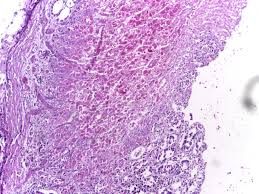

Ходоодны идэгдэлт үрэвсэл

Erosive gastritis (english)

Эрозивный гастрит (ру́сский)